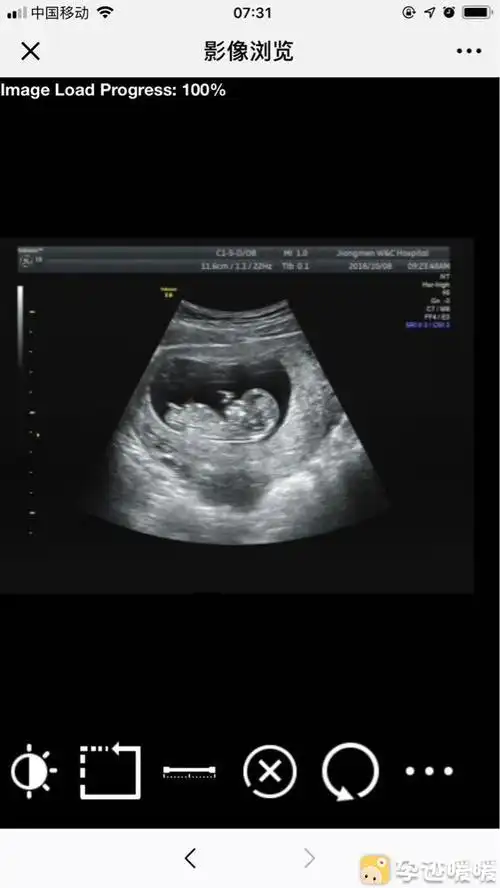

翻12周拍的nt图给大家看看男女.

怀孕十二周可以从b超中的小肿块分辨男女,这真的可以看出来吗?

12周nt顺利通过!感恩!